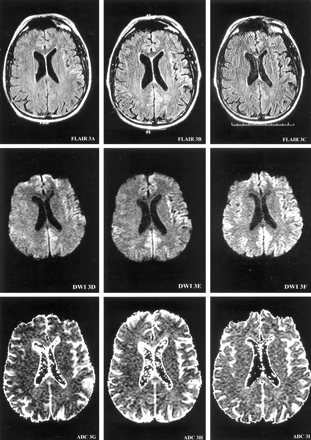

MR imaging of the brain with a DW sequence (9999/98.8 [TR/TE], 5-mm-thick sections, diffusion gradient strength 1000 s/mm2) was performed at 4, 5.5, and 6 months after the onset of symptoms (Fig 1). T1-weighted (566/11.3, 2-ms echo train length [ETL], T2-weighted (4000/102, 16-ms ETL), gadolinium-enhanced T1-weighted (566/11.3, 2-ms ETL), and gradient-echo (750/35) images were consistently normal. At 4 months from onset, DW images demonstrated increased signal intensity in the right temporal cortex in a gyriform pattern. At 5.5 months from onset, the areas of hyperintense signal on DW images involved more cortical gyri and extended to the left temporoparietal cortex. At 6 months from onset, DW images showed a ribbon-like area of hyperintensity involving the right temporoparietal occipital cortex, as well as the left parietal and frontotemporal cortex extending into the parafalcine occipital region (Fig 1). Qualitative apparent diffusion coefficient (ADC) mapping of these regions revealed a decreased signal intensity indicating the presence of restricted diffusion. FLAIR images (10,002/174/2200 [TR/TE/TI]) at 6 months showed subtle hyperintense signal in the left frontotemporal region, corresponding to the observed DW imaging findings (Fig 1). MR proton spectroscopy was performed at 6 months from symptom onset and revealed a slightly decreased ratio of the peaks for N-acetylaspartate to creatine (1.46–1.56 [normal >1.8]) measured in the parafalcine occipital and left frontal cortical regions.

Serial MR images demonstrate the evolution of ribbon-like cortical signal intensity abnormalities. MR images are presented at each of three brain axial levels (1–3), at each of three time points from the onset of symptoms (left columns, 4 months; middle columns, 5.5 months; right columns, 6 months) for FLAIR (top row), DW imaging (middle row), and ADC (bottom row) studies. At 4 months from onset of symptoms, DW images demonstrate gyriform increased signal intensity predominantly in the right temporal cortex (DWI1D) with decreased ADC signal intensity consistent with restricted diffusion (ADC1G). At 5.5 months from onset, the hyperintense signals on DW images involve more cortical gyri, extending into the left temporoparietal cortex (DWI3E). At 6 months from onset, DW images (DWI1F, DWI2F, and DWI3F) show ribbon-like areas of hyperintensity involving the right temporoparietooccipital cortex, as well as the left frontotempoparietal cortex, extending into the parafalcine occipital region.

Images on this page were obtained at level 1.

(continued) Images on this page were obtained at level 2.

(continued) Images on this page were obtained at level 3.